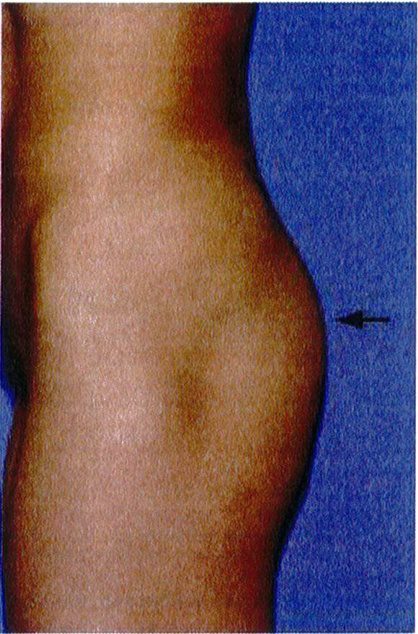

Hai điểm bám cuối cùng của cơ mông phải được đánh giá là ‘khớp nối’ mặt dưới ngoài mông với đùi và ‘khớp nối’ vùng giữa ngoài mông với mặt ngoài đùi. Nếu lý tưởng (Hình 24 và 25), bờ các cơ vùng mông có thể không xác định được vì chúng nối liên tục với khu- ng, thống nhất thành 1 khối. Tuy nhiên, ở một số bệnh nhân, phần bờ ngoài của khối cơ lại xác định được rõ ràng, tạo ra một đường lõm không thẩm mỹ.

Các vùng chuyển tiếp này nên được đánh giá và phân loại là chuyển tiếp liên tục (không thấy mép cơ), vừa phải (đường ranh giới chúng tạo ra không rõ nét), và không liên tục (đường ranh giới rõ nét) (xem hình 24 và 25). Khi sự phân tách này ngày một rõ, nên xem xét để tiêm lipofiller giúp đường chuyển tiếp trở nên liên tục.

Smooth transition: Chuyến tiêp liên tục Moderate demarcation: Trung gian Sharp demarcation: Không liên tục

Hình. 25. Đánh giá vùng chuyển tiếp giữa mặt giữa ngoài mông và hông (mũi tên đen). Vùng chuyển tiếp liên tục được coi là lý tưởng. Các vùng chuyển tiếp khác có thể là trung gian hoặc không liên tục (hình giữa và bên phải). Ở cả 3 bệnh nhân này, điểm C đều không có dấu hiệu lõm.

Smooth transition: Chuyển tiếp liên tục Moderate demarcation: Trung gian Sharp demarcation: Không liên tục